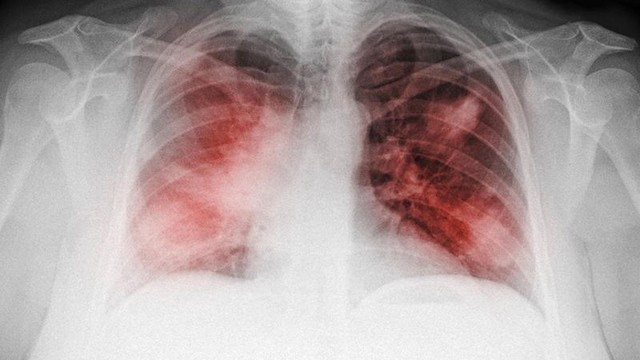

Xơ phổi và ung thư phổi là hai bệnh lý nghiêm trọng liên quan đến hệ hô hấp, nhưng chúng thường bị nhầm lẫn với nhau do có nhiều triệu chứng tương đồng. Vậy xơ phổi có phải ung thư không? Hiểu rõ sự khác biệt giữa hai căn bệnh này là điều quan trọng để có thể chẩn đoán và điều trị kịp thời. Bài viết này sẽ giúp bạn phân biệt xơ phổi và ung thư phổi, đồng thời cung cấp những thông tin cần thiết về nguyên nhân và các biện pháp điều trị hiệu quả.